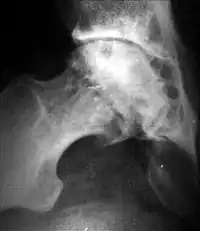

При остеоартрозе утрачивается амортизационная функция суставных хрящей, предохраняющих костную ткань от механических перегрузок. Как компенсация развивается остеосклероз субхондральной губчатой кости. Особенно он выражен при коксартрозе в крыше вертлужной впадины, распространяясь иногда почти на всё тело подвздошной кости. Однако рано или поздно этот механизм компенсации становится недостаточным. Механические силы, передающиеся непосредственно с одной суставной поверхности на другую, вызывают атрофию от давления их наиболее нагружаемых участков и прежде всего центральных отделов суставных головок. Вследствие этого они уплощаются и одновременно расширяются.

Результатом поражения суставных хрящей являются очаговые дистрофические и некротические процессы в субхондральной губчатой кости, соответствующие локальным пикам механических напряжений. В результате этих процессов формируются кистовидные образования. Последние наиболее характерны для коксартроза, при котором они часто множественны и достигают больших размеров (эрозивный артроз).

Рентгенологическое исследование играет важную роль в распознавании этиологических факторов при вторичных остеоартритах. Так, при посттравматическом остеоартрозе оно даёт возможность обнаружить костные деформации после внутрисуставных переломов, установить характерные признаки диспластических артрозов, особенно в тазобедренном суставе, на рентгенограммах можно выявить краевые дефекты суставных поверхностей, остеопороз и атрофию костей при постартритических артрозах. С помощью рентгенографии можно установить связь между отдалёнными от суставов деформациями костей диспластической, посттравматической или иной природы. Например, угловое искривление оси длинной трубчатой кости, сопровождающимися изменениями условий нагрузки на суставы, и вторичным (статическим) остеоартрозом. Рентгенологическое исследование даёт возможность выявить такие причины артроза, как внутрисуставное тело при хондроматозе сустава[20].